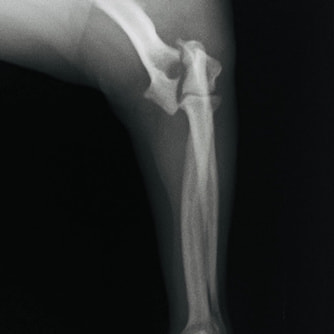

症例3:キルシュナーワイヤーのピンニングによる整復

ペルシャ猫 11ヶ月齢 雄

他院にて左大腿骨遠位の成長板骨折(salter-harrisⅠ型)が認められており、治療相談を目的として来院。当院にて、キルシュナーワイヤーを用いたピンニングにより骨折部位の整復を行いました。術後の経過は良好で、現在も経過観察中です。

術前レントゲン